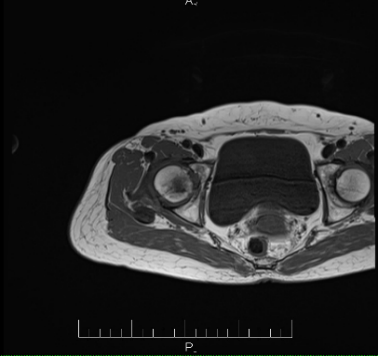

Sau khi chụp MRI kết quả cho thấy tổn thương vùng chỏm xương đùi phải với vùng giảm tín hiệu trên T1,T2, tăng tín hiệu trên STIR, những tổn thương sớm này không thể quan sát thấy được trên chụp Xquang thường quy.

Hình ảnh Xquang và MRI của bệnh nhân

Bệnh nhân được chẩn đoán hoại tử chỏm xương đùi phải giai đoạn II theo phân loại Arlet – Ficat. Với những tổn thương phát hiện sớm như thế này, bệnh nhân sẽ được điều trị nội khoa nhằm bảo tồn khớp háng.